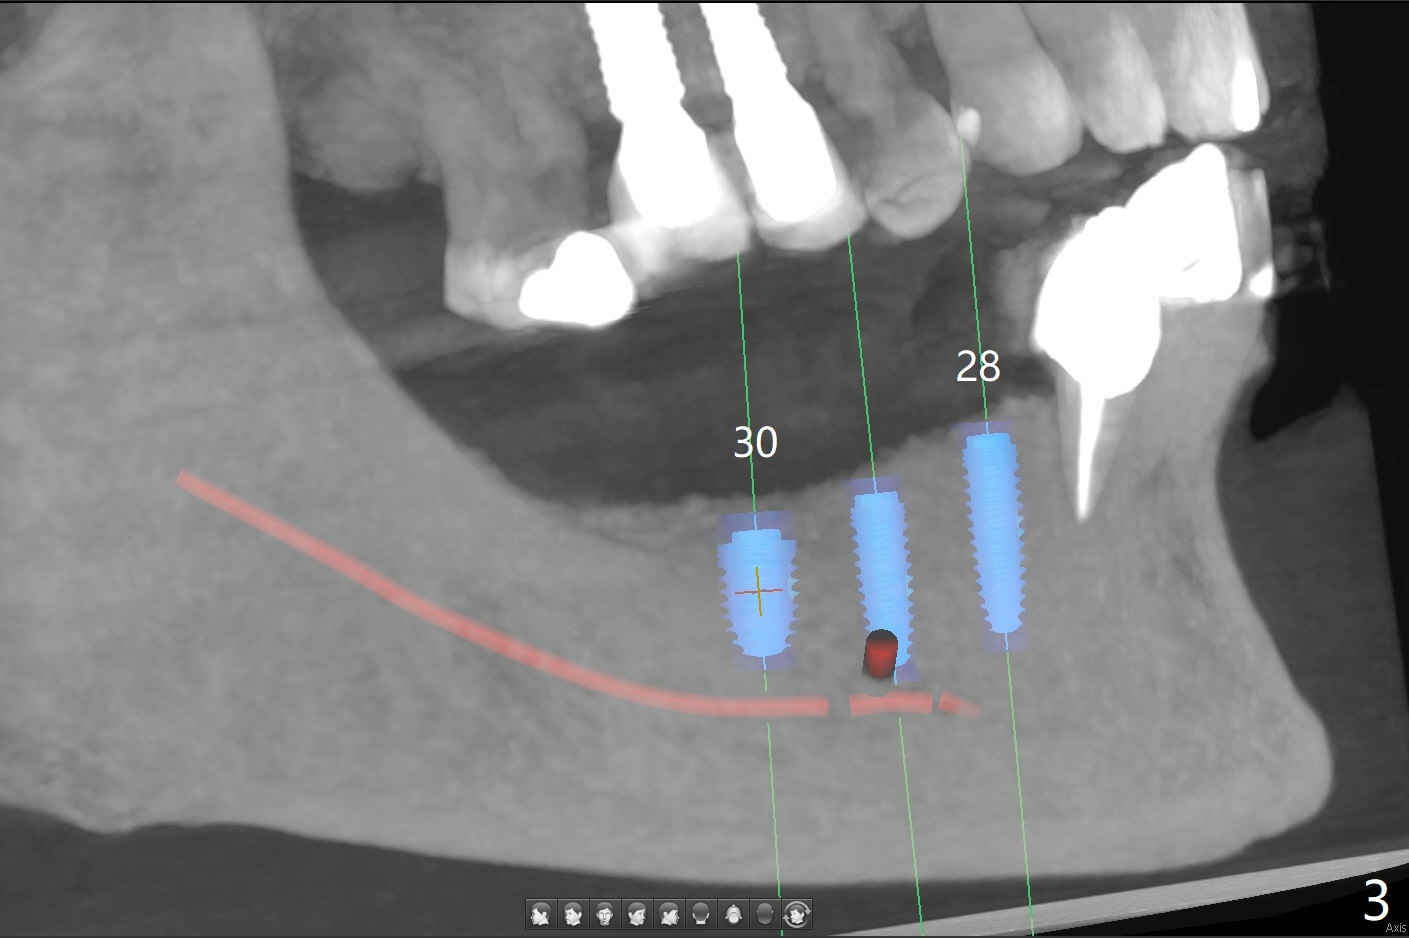

A 69-year-old woman requests conversion of the lower RPD to implant restoration. Initially implants are going to be placed at #19, 28, 29, and 31 (Fig.1,2). CT exam shows short bone at #31 (Fig.2). Please try to place implants at #28-30 for a cantilever FPD (Fig.3) if reasonable. When making guide(s), please use #18 residual roots as a distal stopper (Fig.1) if practical.